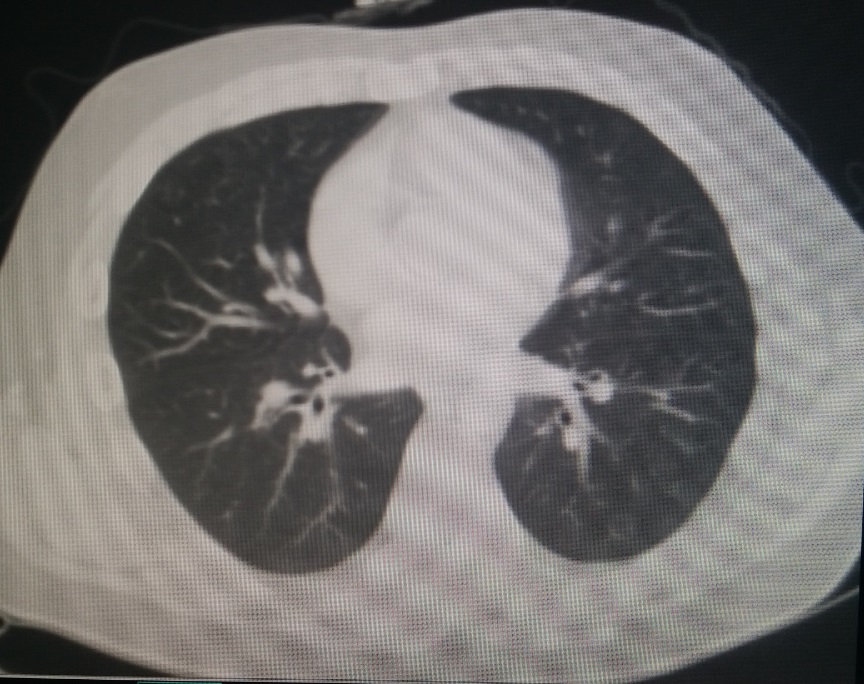

患者入院后,体检发现,其身体较为肥胖,胸廓整体外观为桶状,体表脂肪较多,但前胸壁骨性结构明显前突(图1,2,3)。X线检查,正位片提示肋间隙宽度正常,肺野肺纹理正常,无肺气肿征象(图4),侧位片提示前胸壁整体前突(图5)。行CT检查,胸廓整体呈现桶状,胸壁前后径增加,截面外观接近圆形,肺野无异常(图6)。胸廓顶部桶状不明显(图7),但从心底部水平开始(图8),前胸壁前突逐渐加重,一直延续到肋弓水平(图9,10)。三维重建显示桶状外观(图11,12)。

图6,CT截面图,胸廓呈圆形,肺野无异常。